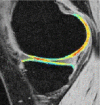

Purpose: To longitudinally evaluate cartilage matrix changes by using magnetic resonance (MR) imaging T1(ρ) (T1 relaxation time in rotating frame) and T2 quantification and to study the relationship between meniscal damage and cartilage degeneration in anterior cruciate ligament (ACL)-reconstructed knees.

Materials and methods: This was an institutional review board-approved, HIPAA-compliant study. Informed consent was obtained. Twelve patients with acute ACL injuries were imaged with 3.0-T MR imaging at baseline (after injury and prior to ACL reconstruction) and 1 year after ACL reconstruction. Ten age-matched healthy subjects were studied as controls. Cartilage T1(ρ) and T2 were quantified in full thickness, superficial, and deep layers of defined subcompartments at baseline and follow-up in ACL-injured knees and were compared with measures acquired in matched regions of control knees. Meniscal lesions were graded by using modified subscores of the Whole-Organ Magnetic Resonance Imaging Score system.

Results: T1(ρ) values of the posterolateral tibial cartilage in ACL-injured knees were significantly elevated at baseline compared with T1(ρ)values of control knees and were not fully recovered at 1-year follow-up. T1(ρ) values of weight-bearing medial femorotibial cartilage in ACL-injured knees were significantly elevated at 1-year follow-up compared with those of control knees. No significant differences in T2 values between ACL-injured and control knees were found. Patients with lesions in the posterior horn of the medial meniscus showed a greater increase of T1(ρ) and T2 from baseline to follow-up in adjacent cartilage than patients without lesions in the medial meniscus.

Conclusion: Quantitative MR imaging T1(ρ) and T2 enable detection of changes in the cartilage matrix of ACL-reconstructed knees as early as 1 year after ACL reconstruction.